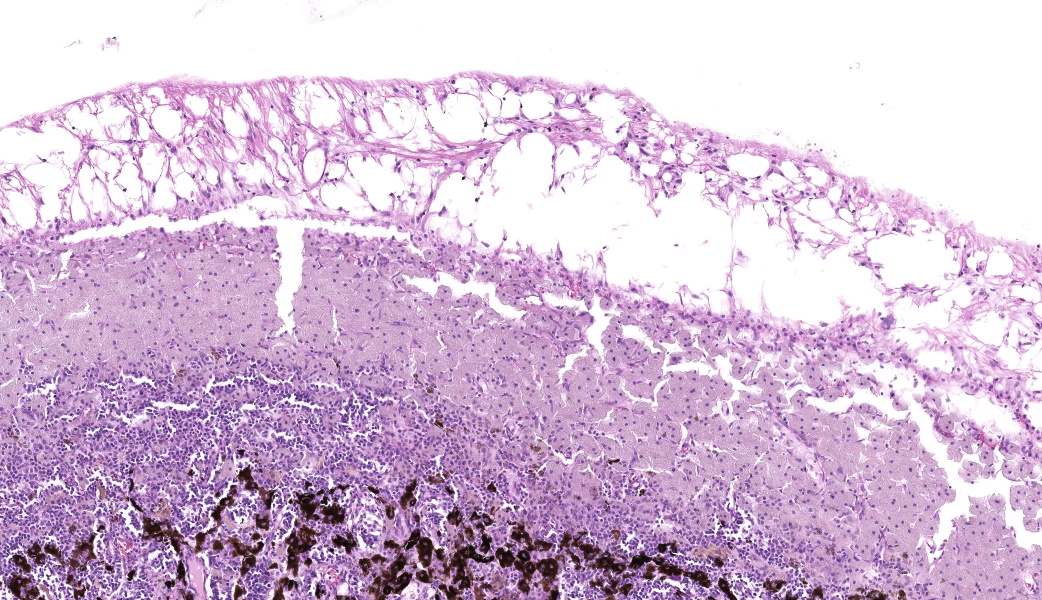

Expanding the anterior uvea, effacing the iris, and markedly expanding the suprachoroidal space is a densely cellular, unencapsulated neoplasm of neuroepithelial cells. Neoplastic cells are arranged in variably dense sheets and as palisading columnar cells surrounding a central lumen (Flexner-Wintersteiner rosettes) or surrounding eosinophilic fibrillar material (Homer-Wright rosettes) surrounded by collagenous and occasionally myxomatous stroma. Neoplastic cells are polygonal to fusiform, have a high nuclear to cytoplasmic ratio, and have distinct cell borders. The nuclei are round to ovoid, finely stippled, and have indistinct nucleoli. There are 16 mitoses in 10 high power fields and anisokaryosis is mild. The neoplastic cells are impinging upon the optic nerve, which has multifocal axonal degeneration and is infiltrated by a population of histiocytes, lymphocytes, and plasma cells, as well as scattered foci of hemorrhage. The retina has multifocal, disorderly components of viable photoreceptor and retinal ganglion cells, dense necrosis, glial scarring, and presumed Mueller cells. The retina is diffusely detached and lacks apparent retinal vessels. The retinal pigment epithelial cells have multifocally migrated through to the inner layers of the retina. The cortical lens fibers are moderately liquefied and homogenous and there is posterior migration of the lens epithelium, consistent with cataractous change. The corneal epithelium has marked, segmental ulceration and the outer corneal stroma in this area is mineralized with occasional breaks and is densely compact with fibrosis. Multifocally throughout the corneal stroma are areas of fibrosis, vascularization, and scattered neutrophils.Contributor's Morphologic Diagnoses:

Lastly, there was much discussion on the extensive secondary changes seen in this eye histologically, including keratitis and panuveitis. It is the opinion of conference participants that these changes were likely secondary to the medulloepithelioma and, as such, favored a traditional JPC morphologic diagnosis in such cases which is limited to the tumor and anatomic locations within the globe. This is not to say that the secondary changes are unimportant or should not be listed, but in true JPC tradition, changes secondary to a tumor are not included in the morphologic diagnosis.